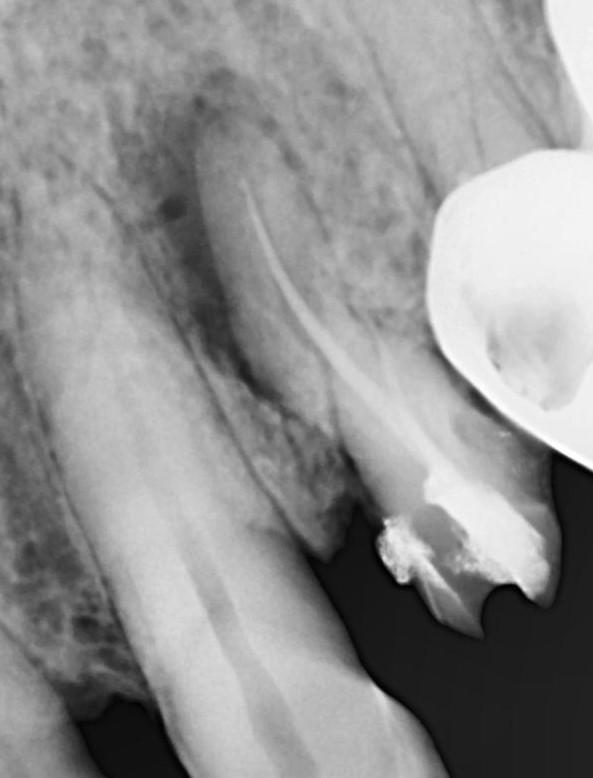

Tooth : 2-4 / UR first premolar . History : Endo with PFM crown made around one and a half ago ( elsewhere)

Patient reported with swelling around crown. IOPA show large periapical around 2-4. I remove dthe PFM crown. See images below.

There also seems to be root fracture.

What is the prognosis of this tooth ? Should a retreatment be attempted ?